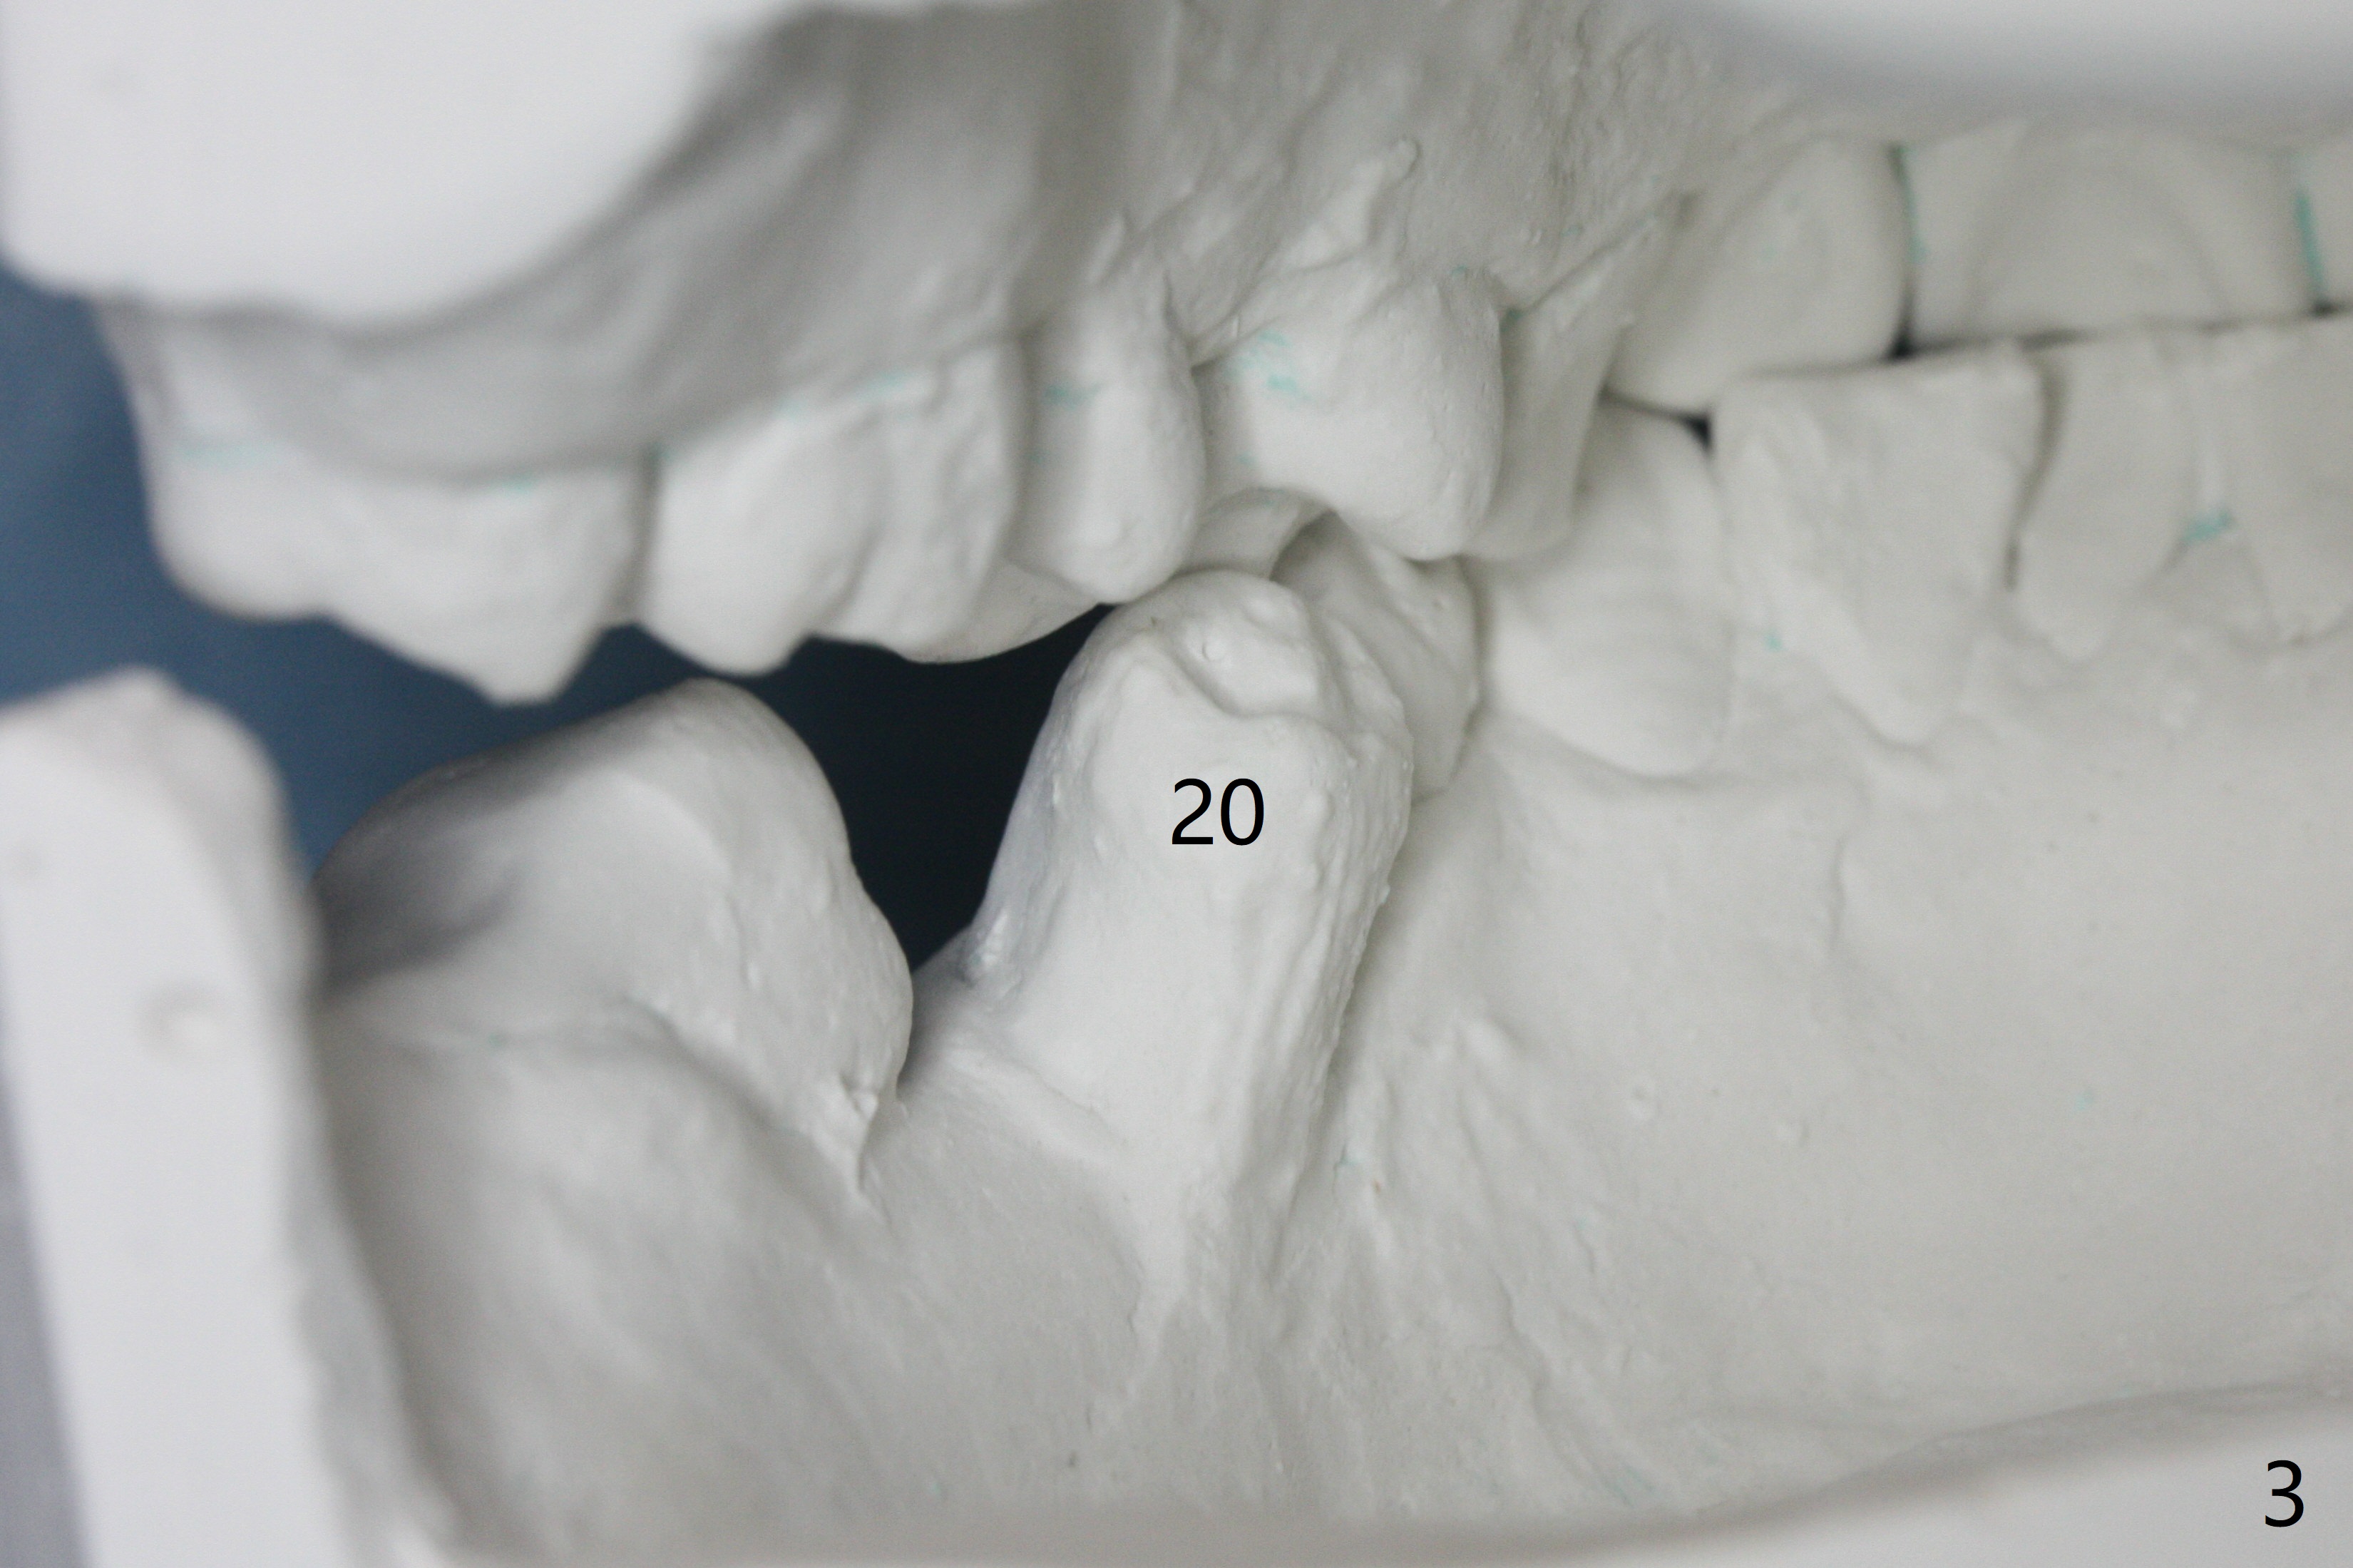

A 43-year-old man has poor dentition on the left: 1st molar missing, 2nd molar mesial inclination (Fig.1) and 2nd bicuspid lingual tilt (Fig.2). The latter is nonfunctional (Fig.3 (linguoposterior view). Two molar implants will be placed in a position so that their crowns will be in cross bite (Fig.4,5), the same occlusal scheme as the teeth #21 and 22. When these implants osteointegrate, the provisional crowns (Fig.6 P) will be supraocclusal so that there is clearance (*) for #20 to upright orthodontically (Fig.7-9). Moreover, these implants will be used anchorage as well as #21 and 22. Panoramic X-ray (Fig.1) and CBCT (Fig.10-12) show limited bone height at the sites of #18 and 19. It appears that 5x8 and 5.9x6 mm implants are appropriate with ridge reduction at #19.